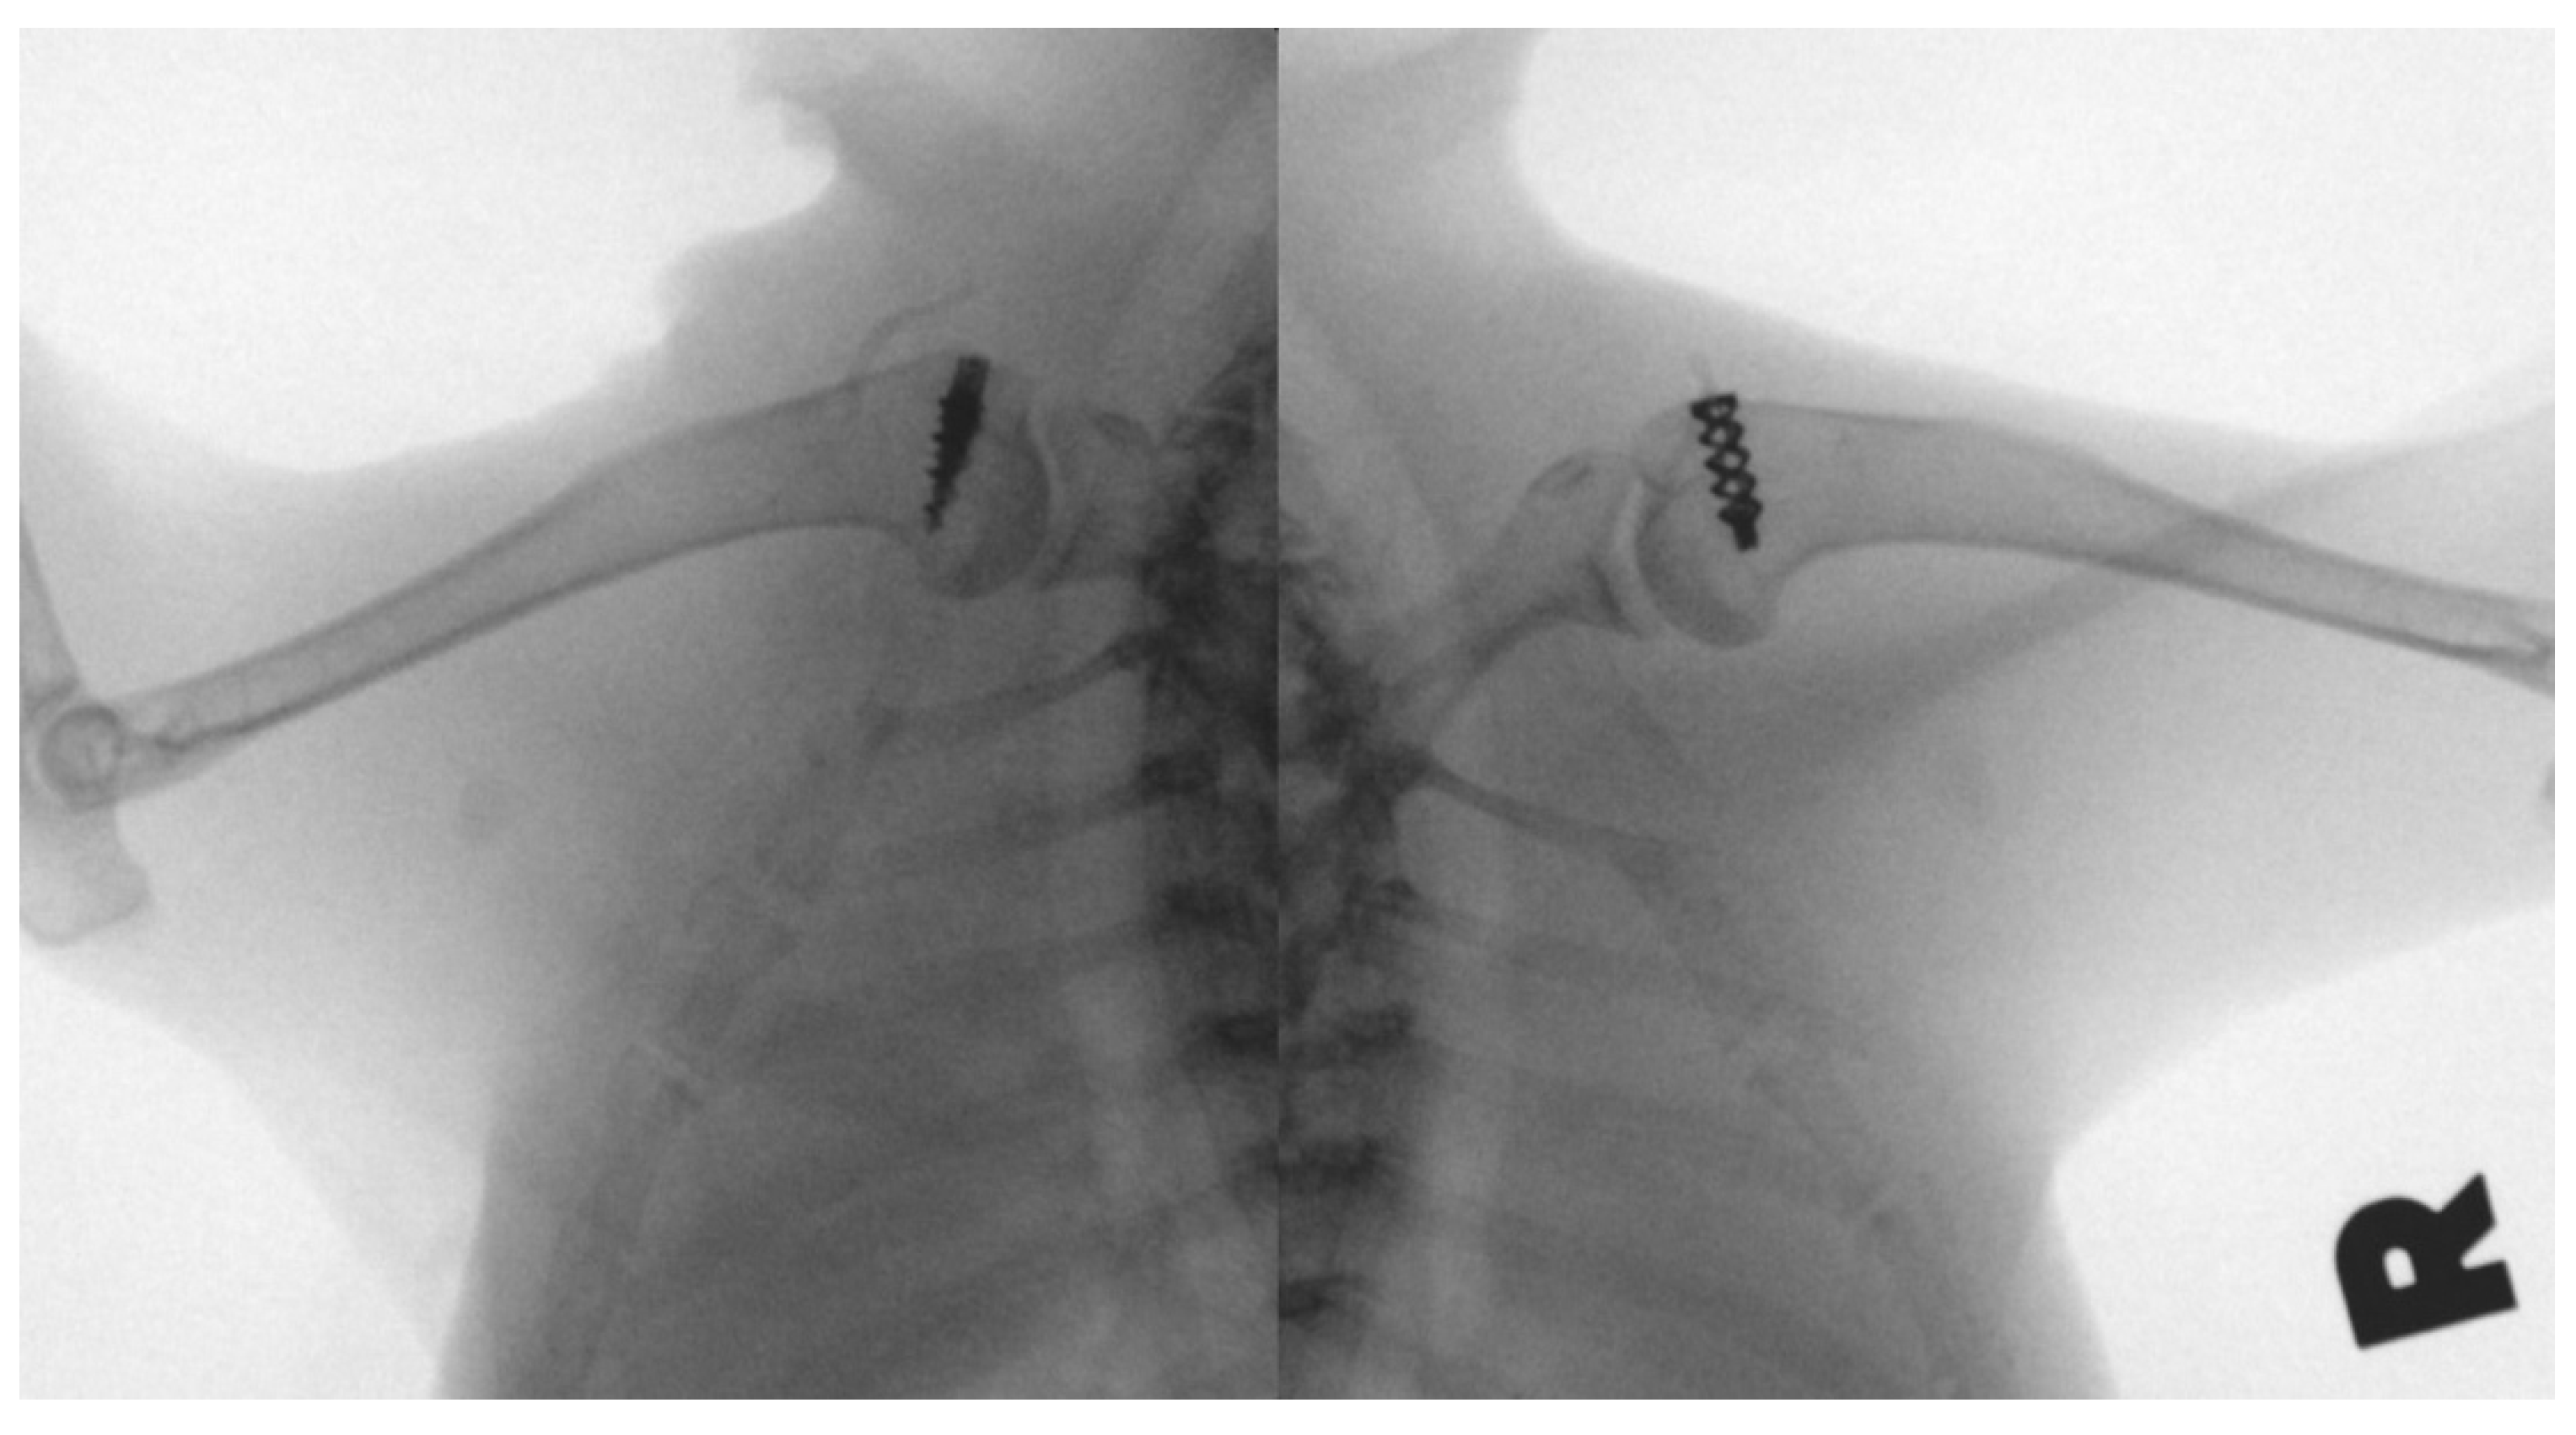

2.4. Surgical Methods

3.5. Micro-CT Analysis